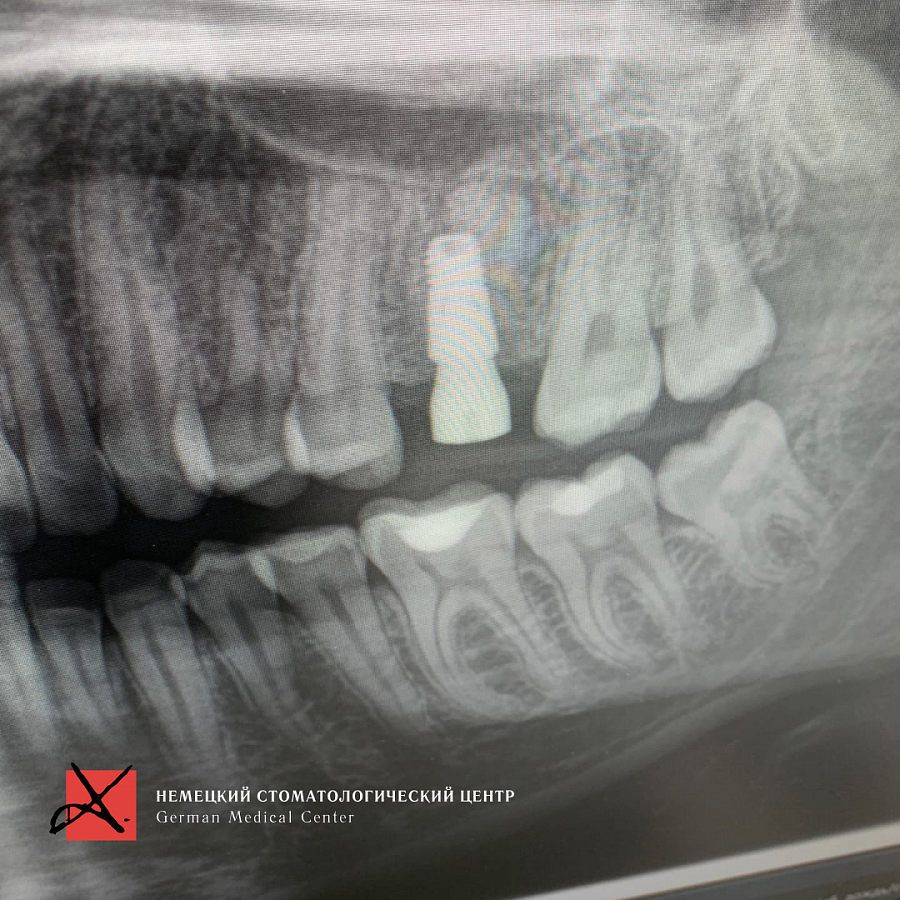

На рентгеновском снимке виден костный дефект после удаления, а также перелом вестибулярной стенки.Этапы лечения

Провели костную пластику с последующей имплантацией. Материал для пластики - Geistlich Bio - Oss ( Био Осс ) - натуральный костнозамещающий материал, покрытый мембраной. Через 6 месяцев провели имплантацию и далее протезирование.